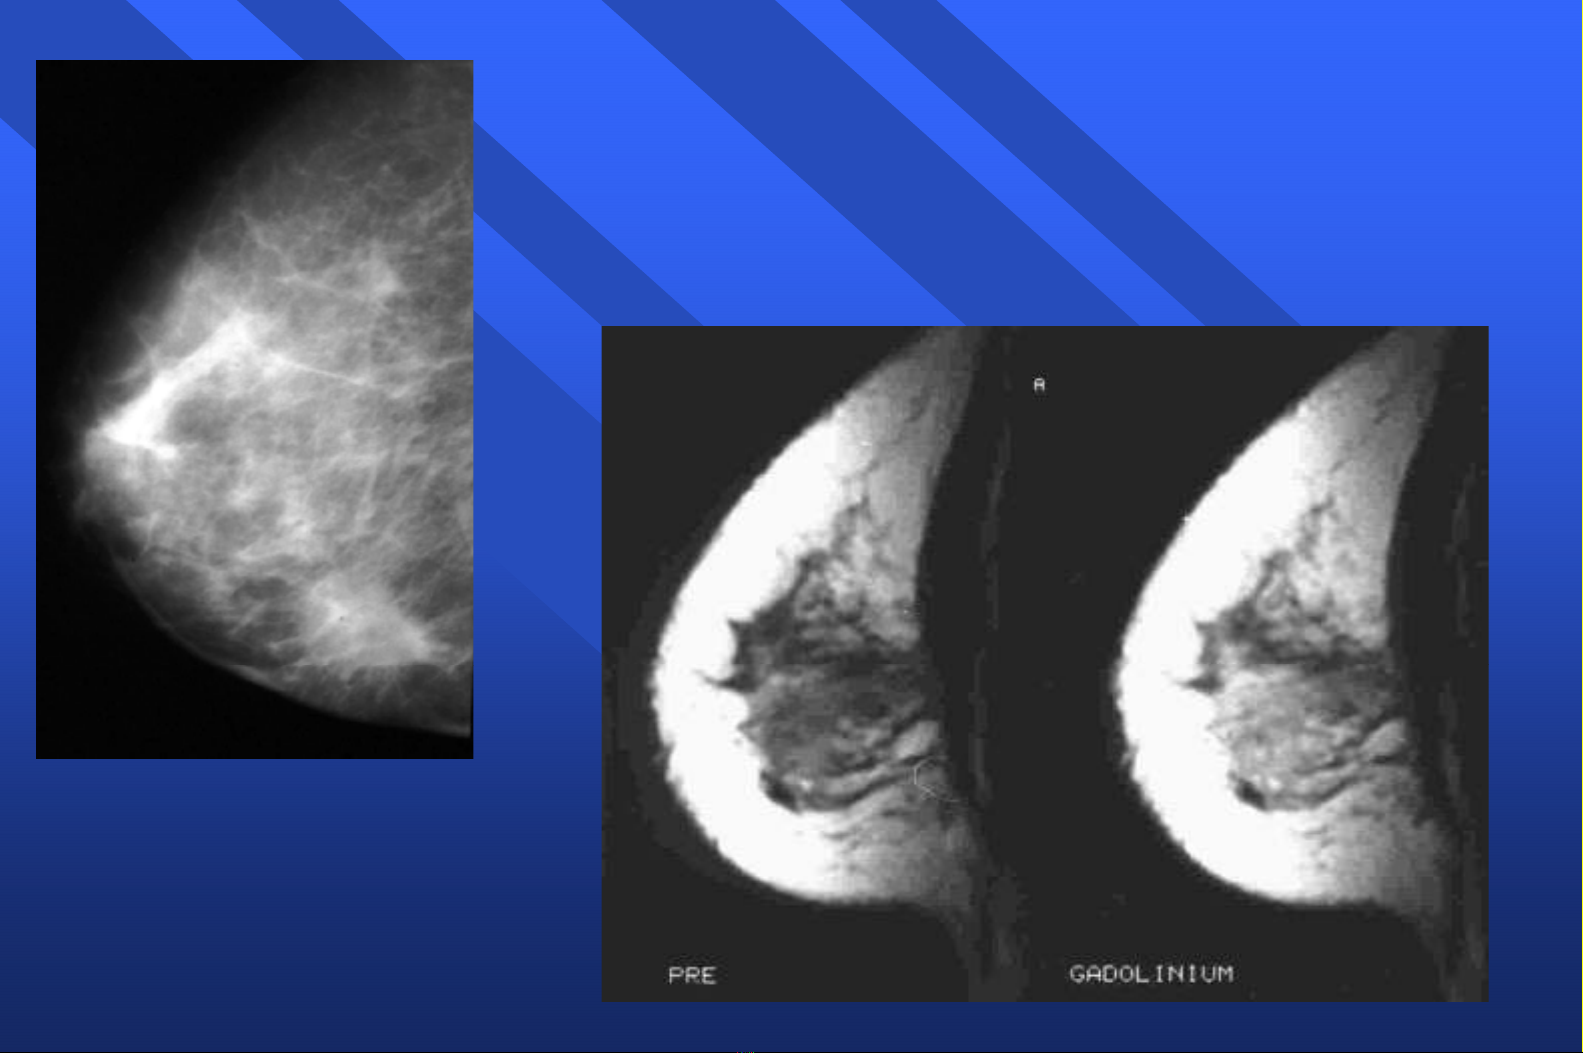

Bơm

BơmGadolinium

Gadolinium :